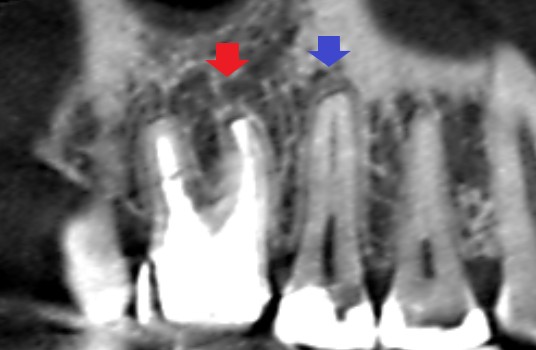

初診時の矢状断のCT画像です。

矢印の先に影がみられます。赤い矢印の先にある影は、第一大臼歯の根の先にできている膿です。青い矢印の先にある影は、第二小臼歯にできていたむし歯の影響で、歯髄の炎症が根の外まで波及して歯槽骨の吸収が起こっていることが考えられました。